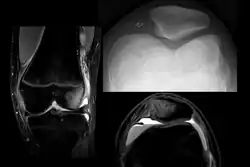

On X-ray, with skyline projections, dislocations are readily diagnosed. In borderline cases of subluxation, the following measurements can be helpful:

- The lateral patellofemoral angle, formed by:[16]

- A line connecting the most anterior points of the medial and lateral facets of the trochlea.

- A tangent to the lateral facet of the patella.

- With the knee in 20° flexed, this angle should normally open laterally.[16]

- The patellofemoral index is the ratio between the thickness of the medial joint space and the lateral joint space (L). With the knee 20° flexed, it should measure 1.6 or less.[16]